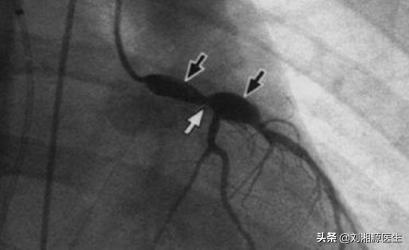

3)川崎病过去又叫黏膜皮肤淋巴结综合征,几乎只发生于婴幼儿,临床常表现为发热、皮疹、颈部非化脓性淋巴结肿大、眼结合膜充血、口腔黏膜弥漫充血、杨梅舌、掌跖红斑、手足硬性水肿等,累及冠状动脉(见图4)时预后不佳。

图4 川崎病冠状动脉造影提示明显扩张